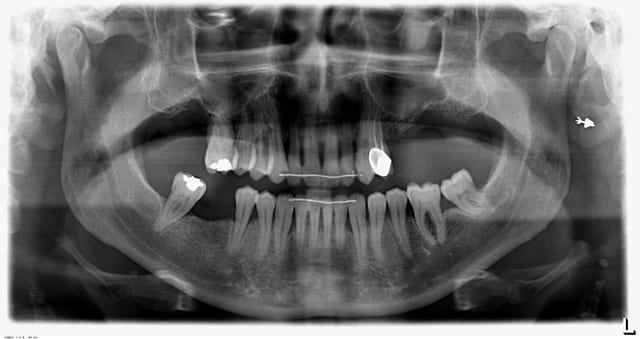

Je l'ai motivé, fais des surfacages et contentions. Le contrôle de plaque est meilleur mais reste moyen. Je joins la pano après surfacages et extractions de 25 26 27 et 17 il y a trois mois.

Moi je pensais peut être proposer deux implants en 25 et 46.

vu la radio, c'est mal parti... tu poses l'implant en 46 mais son antagonsite, la 16, semble être perdue à moyen terme, tu mettras un implant en 16 dans 1 an......etc pour les autres dents. Faut bien voir avec le patient, car il risque d'en avoir marre si tu proposes tous les ans de nouveaux implants + couronnes.

Mais ce sera aussi difficile de passer à un bridge complet sur implants vu la radio....

Y'a t-il une atteinte de furcation sur 36?

Les dents maxillaires me semblent perdues à moyen terme.

Les molaires mandibulaires également.